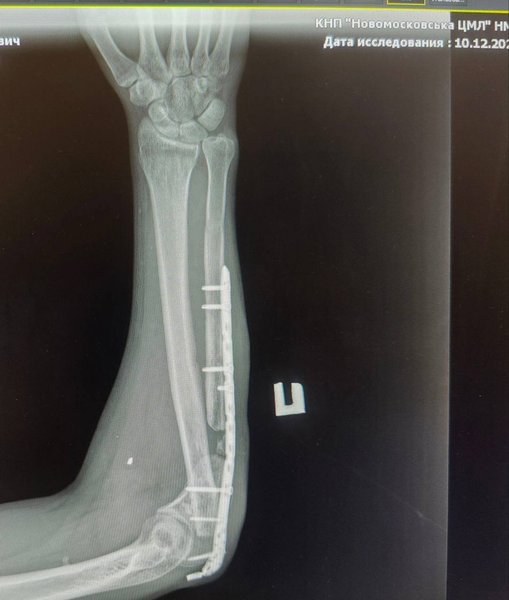

В канале бригады появилась история бойца с позывным "Ямаха". Побратимы опубликовали его фото во время реабилитации после ранения. Они показали, как выглядит травмированная рука: сначала она была искривлена, потом внутрь вставили металлический стержень, который видно на рентгене. Ситуация была настолько сложная, что угрожала ампутация ноги, но ее удалось спасти. Кроме того, граждане собирали деньги на помощь бойцу.